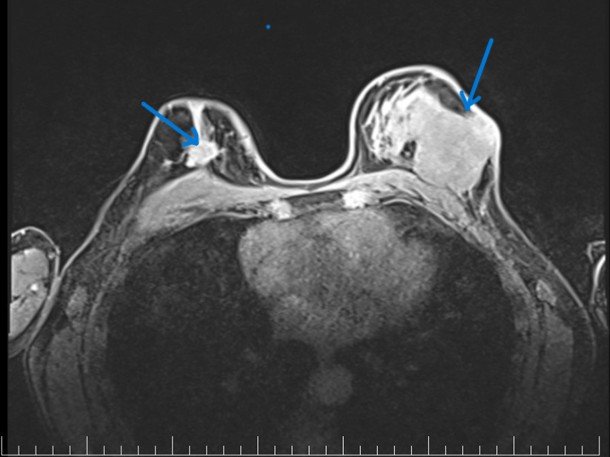

MRI (mágneses rezonancia) felvétel kétoldali mellrákról (nyilak jelzik a daganatot)

Fotó: Amethyst sugárterápiás központ

„Korábban a sikeres kezelések után azt mondtuk, hogy öt év elteltével meggyógyult a beteg. Ez mára megváltozott, mert látjuk, hogy a betegség akár öt év után is kiújulhat, sőt egy melldaganat esetében akár 10–15–20 év elteltével is megjelenhet egy újabb daganat, amelynek nincs köze az előzőhöz. Ezért a betegeket az ötéves időszak után is rendszeres ellenőrzésekre hívjuk vissza” – magyarázza az orvosnő.